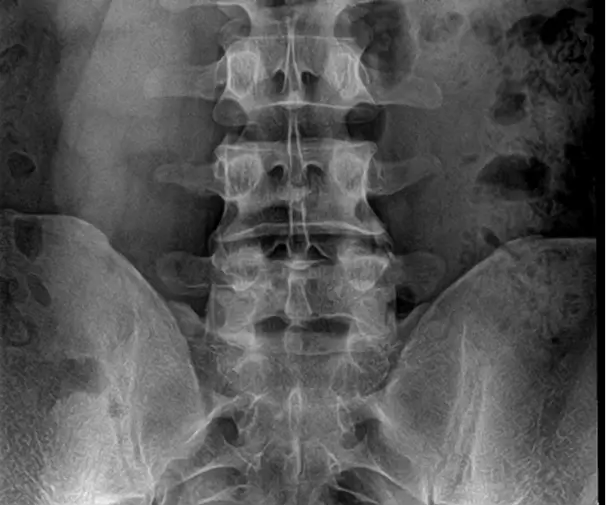

Pre OP radiographs, frontal and sagittal views